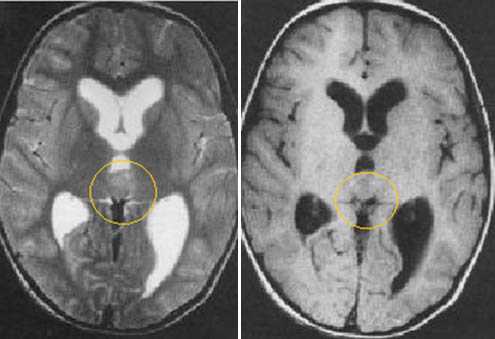

Пиллоидная астроцитома задних отделов III желудочка. Определяется небольших размеров образование с развитием окклюзионной гидроцефалии. Опухоль практически не отличается по сигналам от вещества головного мозга. После в/в контрастирование отмечается усиление МР-сигнала от образование, что позволяет уточнить расположение опухоли, степень компрессии четверохолмной пластинки и водопровода мозга.

Эпендимома задних отделов III желудочка. Определяется объемное образование в задних отделах шишковидной железы. Передние бугорки четверохолмия оттеснены вниз. Водопровод мозга сдавлен.